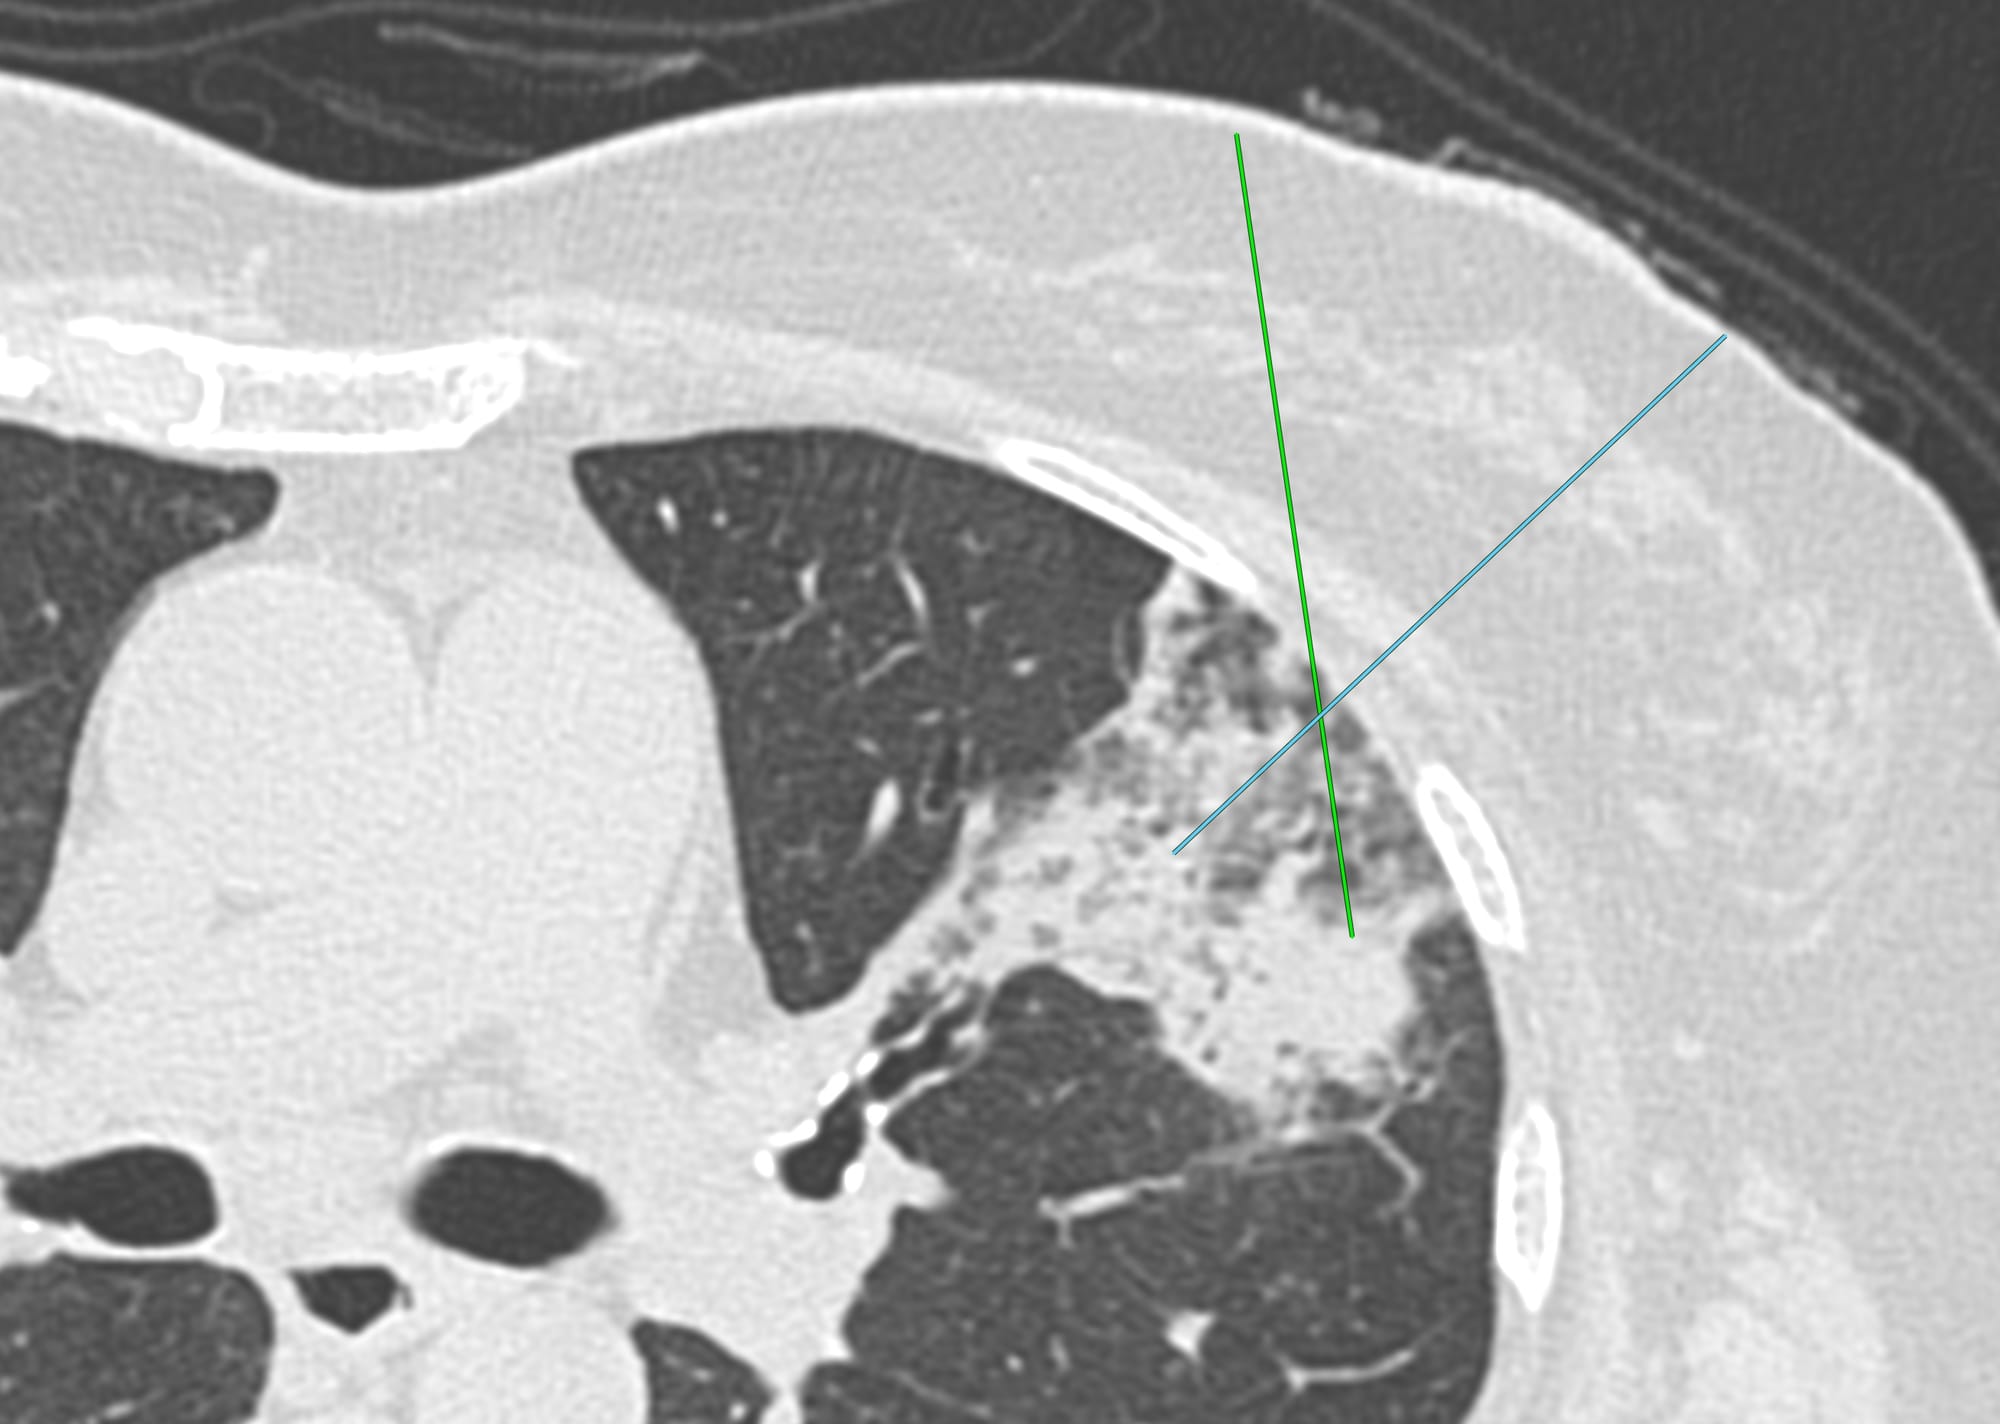

59-years old with fever and non-resolving consolidation

What would be your approach?

The video below describes the case and the reason for performing a biopsy parallel to the vessels and not perpendicular